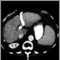

CT of the abdomenDefinition Return to top

An abdominal CT scan is an imaging method that uses x-rays to create cross-sectional pictures of the belly area. CT stands for computed tomography.